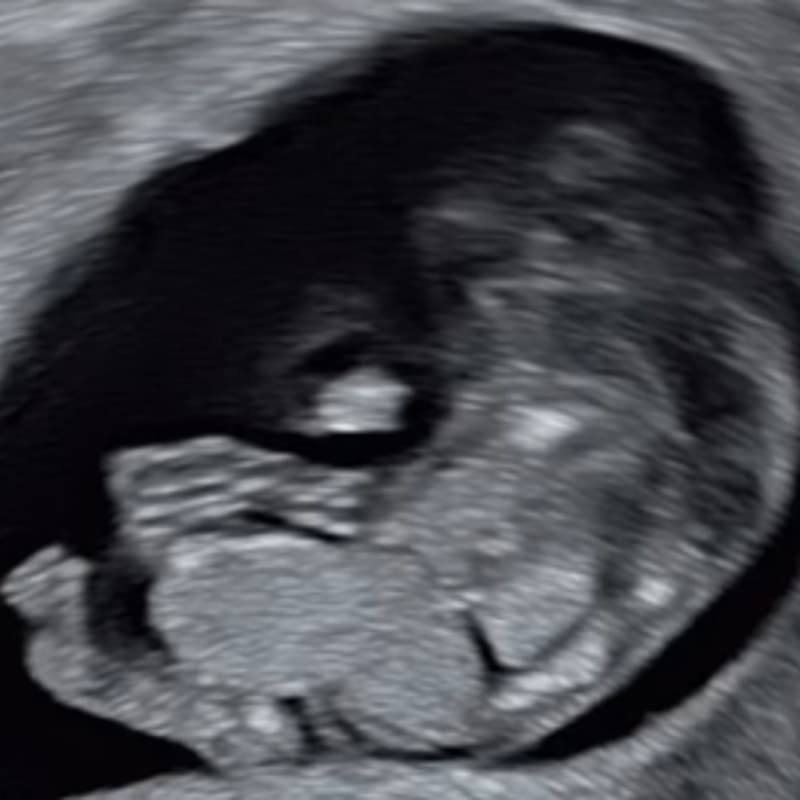

Cover Image for Fetal Imaging Spotter Cases with Dr Gita Krishna Puppala

Fetal Imaging Spotter Cases with Dr Gita Krishna Puppala

Fetal Imaging Spotter Cases